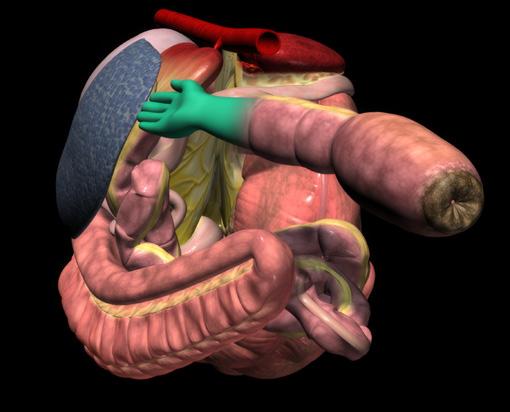

76 Reduce recurring entrapment colic

Jackie Bellamy-Zions talks to Dr. Nicola Cribb about new research showing how preventative surgery can reduce the risk of recurrent nephrosplenic entrapment colic in horses.